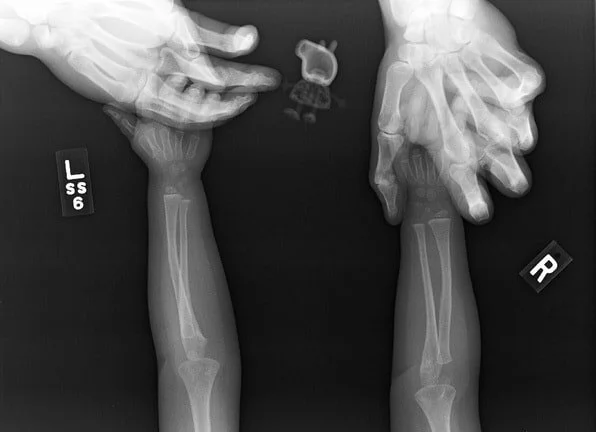

6. Для тех, кто не видел птичий рентген

7. Что будет, если чихнуть во время рентгена